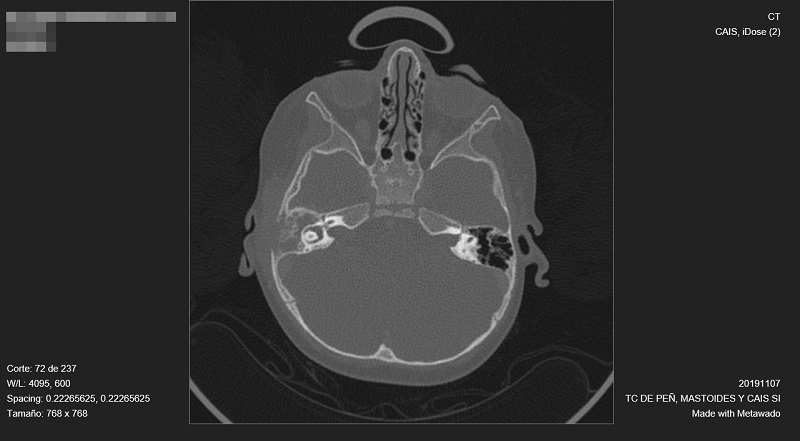

Al no observarse mejoría clínica, se decide realizar una tomografía computarizada (Fig. 1), en la que se observa ocupación completa con intensa destrucción ósea del conducto auditivo, oído medio y mastoides derechas.

| Figura 1. Tomografía computarizada. Intensa destrucción ósea del conducto auditivo, oído medio y mastoides derechas |